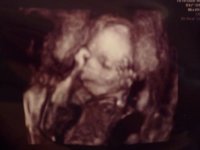

It's not really a big newsflash or anything but I just wanted to share some of my excitement by telling you all that...

I've booked a 4D scan!

Has anyone else had one? Did yours turn out good? xxx